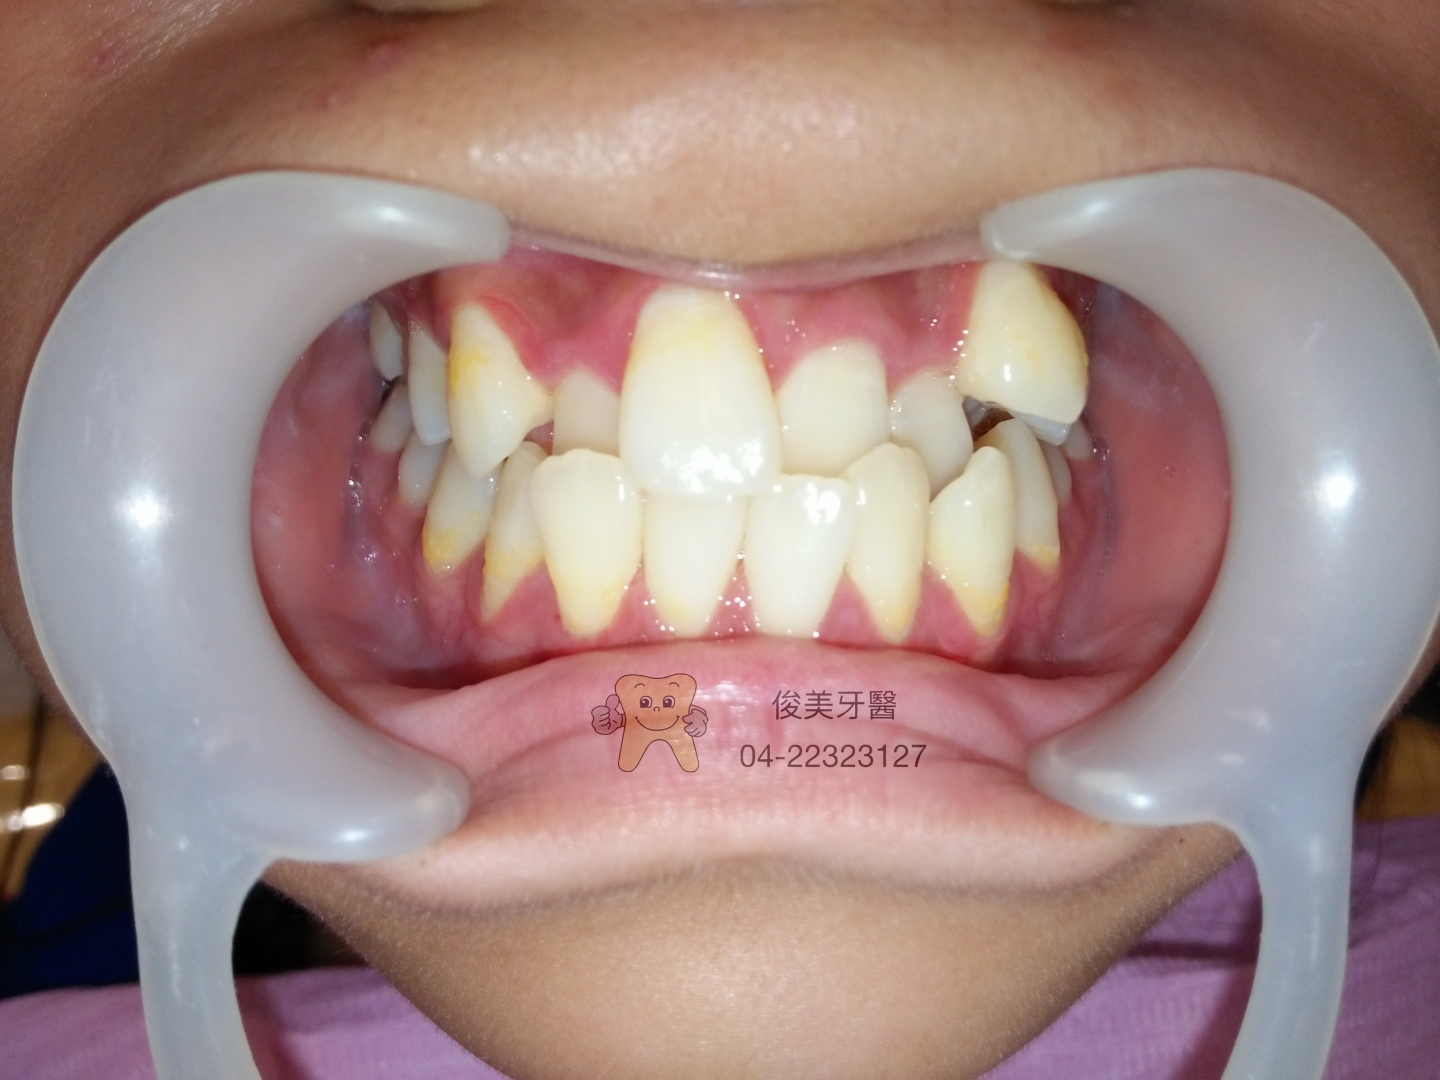

患者原始狀況。牙齒重疊,牙齦有點紅腫,牙齒頸部刷不乾淨。

重疊的牙齒縫裡有蛀牙 。